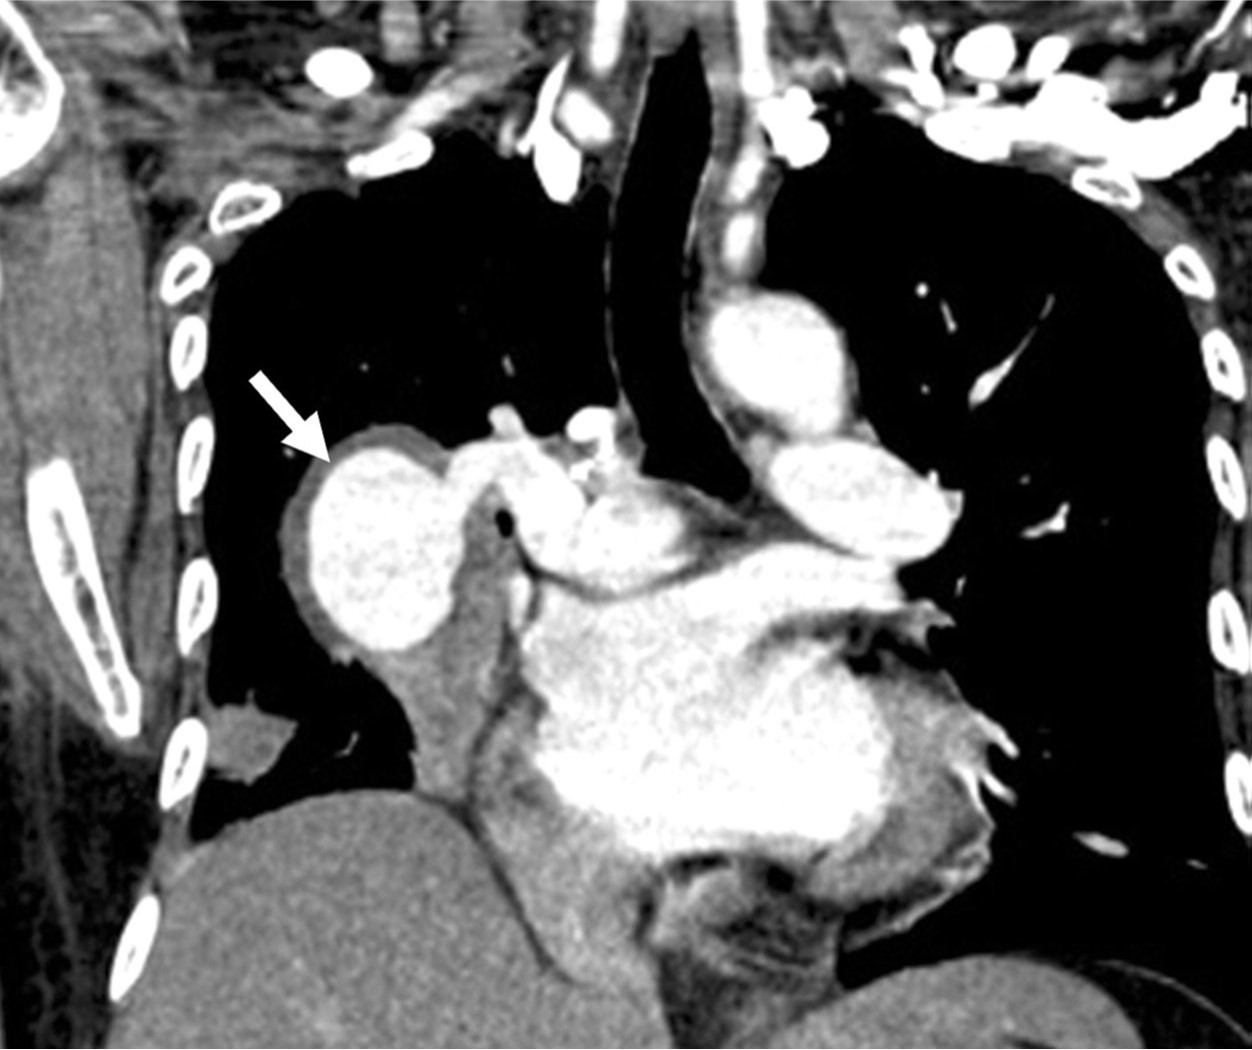

Fig. 1. A

Fig. 1A, B. The axial (A) and coronal (B) images of chest CT scan demonstrate a pseudoaneurysm (arrows) in the right lower lobe, connected to the proximal part of the right lower pulmonary artery.

Fig. 1. B